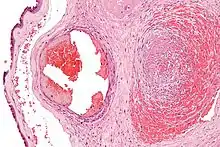

Excessive generation of fibrin due to activation of the coagulation cascade leads to thrombosis, the blockage of a vessel by an agglutination of red blood cells, platelets, polymerized fibrin and other components. Ineffective generation or premature lysis of fibrin increases the likelihood of a hemorrhage.